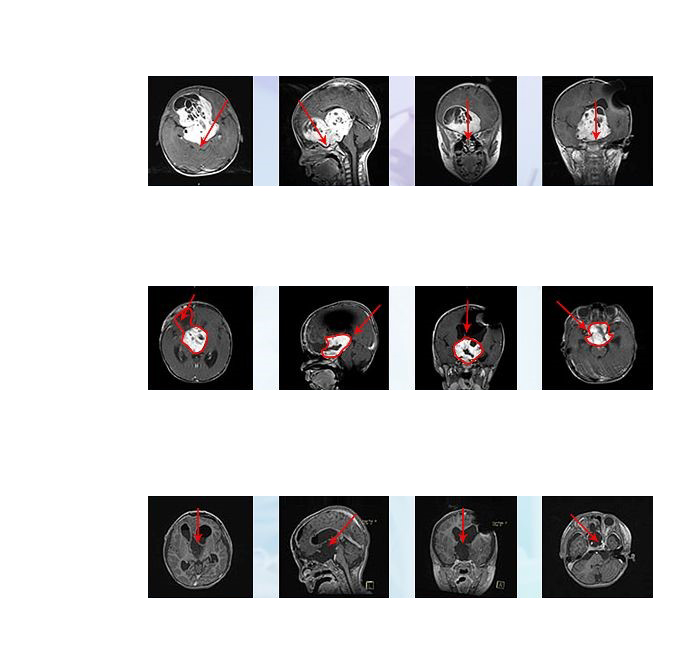

視神經(jīng)膠質(zhì)瘤的影像學(xué)表現(xiàn)

X線:平片檢査可發(fā)現(xiàn)一側(cè)視神經(jīng)孔擴(kuò)大,邊緣銳利圓滑,提示腫瘤較大并侵及顱內(nèi)。

CT:表現(xiàn)為視神經(jīng)條帶狀或梭形增粗,邊界光整清楚。腫瘤累及眶尖時(shí)致其脂肪消失。腫瘤密度均勻,CT值在40-60HU之間,輕度強(qiáng)化,有時(shí)其內(nèi)可見無強(qiáng)化低密度區(qū)。增強(qiáng)檢査要注意觀察腫瘤向視神經(jīng)管內(nèi)段或顱內(nèi)段的侵及:侵及管內(nèi)段而引起視神經(jīng)管擴(kuò)大;侵及顱內(nèi)段及視交叉則在鞍上池內(nèi)形成腫塊。無鈣化表現(xiàn)。

MRI:表現(xiàn)為T1WI中等偏低信號(hào),T2WI明顯高信號(hào)。腫瘤累及視神經(jīng)管內(nèi)段時(shí),多引起眶內(nèi)段蛛網(wǎng)膜下腔腦脊液循環(huán)受阻,引起蛛網(wǎng)膜下腔明顯增寬,顯示為病變周圍長T1長T2信號(hào),與腦脊液信號(hào)一致。增強(qiáng)后腫瘤呈較明顯強(qiáng)化。

德國的手術(shù)之旅較為順利,巴特朗菲教授通過額骨顱骨開顱術(shù)和大腦半球間穹窿入路腫瘤切除術(shù)直至Monro孔(室間孔),并沿著腦室壁向中腦行進(jìn)。小冬右側(cè)的視神經(jīng)被腫瘤浸潤包裹,但是左側(cè)視神經(jīng)被小心地從腫瘤腫塊中剝離出來,垂體腺和垂體柄也被小心的保護(hù)起來。

術(shù)后患兒有一過性發(fā)熱和尿崩,均很快控制好轉(zhuǎn),一周后出ICU病房,術(shù)后2周左右患兒視力有輕微好轉(zhuǎn),2周后出院,且能站立和短距離行走,較入院前好轉(zhuǎn)明顯。2019年4月復(fù)診時(shí)未見復(fù)發(fā),且視力逐漸恢復(fù),可以分辨人影和準(zhǔn)確抓拿物品?;純?a href='/qianyan/naozhongliu/' target='_blank'>腦腫瘤得到了大概率以上的切除,術(shù)前岌岌可危的視力也保住了。術(shù)后病理顯示毛細(xì)胞型星形細(xì)胞瘤,WHO I級(jí),低級(jí)別膠質(zhì)瘤。研究顯示其中位生存期可長達(dá)50年,腫瘤近全切手術(shù)之后可與正常孩子生存時(shí)間無異。

此次在德國INI的二次手術(shù),從術(shù)前侵襲至雙側(cè)額葉及三腦室的較大瘤體,到術(shù)后影像上未見瘤體,從幾近失明到逐漸地視力恢復(fù)接近正常,小冬的手術(shù)效果可以說是教科書級(jí)的示范案例。